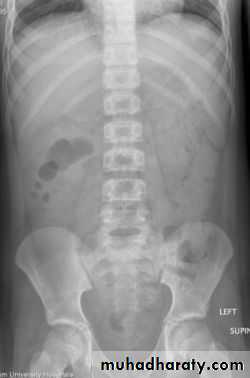

Dilatation of the bowel

Dilatation of the bowel is the cardinal plain film sign of intestinal obstruction

If the bowel is dilated it is important to try and decide which portion is involved

The valvulae conniventes (seen in proximal and mid small bowel) are always closer together than the colonic haustra and cross the width of the bowel , often giving "stack of coins" appearance

The colonic haustra ,which usually form incomplete bands across the colonic gas shadows, are always present in the ascending and transverse colon, but may be absent distal to the splenic flexure

Small bowel obstruction

Large bowel obstruction

Valvulae conniventes

Present

Absent

Number of loops

Many

Few

Distribution of loops

Central

Peripheral

Haustra

Diameter

3 – 5 cm

More than 5 cm

Radius of curvature

Small

Large

Fecal material